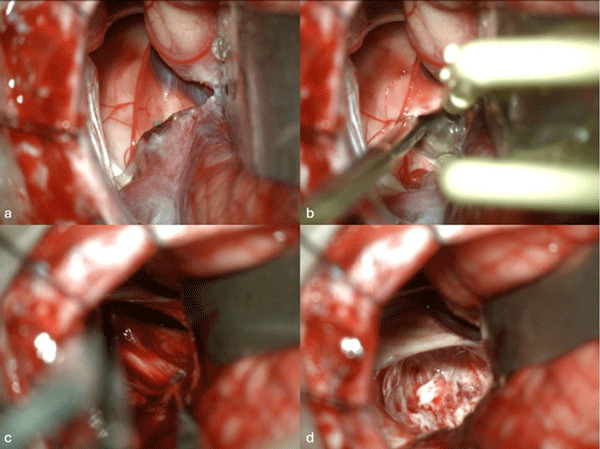

Caso 3: cavernoma pontino

Un hombre de 37 años, con antecedentes de hipertensión arterial, debutó con ataxia de la marcha, nistagmo y hemihipoestesia facial izquierda y braquiocrural derecha. La RM de encéfalo evidenció una malformación cavernomatosa centrada en la protuberancia y el pedúnculo cerebeloso medio izquierdo (Figura 6). Un mes después del sangrado, el paciente fue sometido a una exéresis de la lesión mediante un abordaje retrosigmoideo ampliado por izquierda a través del pedúnculo cerebeloso medio (Figura 7), logrando una exéresis completa (Figura 8). Después del procedimiento, el paciente evolucionó con persistencia de los síntomas de ingreso, pero sin agregar nuevos déficits.

Figura 6. RM preoperatoria de encéfalo. Se evidencia una lesión única intraaxial localizada en el puente y pedúnculo cerebeloso medio izquierdo, hiperintensa en T1 y con un anillo hipointenso en T2, característica de una malformación cavernomatosa con sangrado reciente. A) Imagen ponderada en T1 en corte sagital. B y C) Imágenes ponderadas en T2 en cortes axial y coronal, respectivamente.

Figura 7. Imágenes intraoperatorias bajo microscopía. Abordaje retrosigmoideo ampliado a izquierda, con ruta de ingreso transpedúnculo cerebeloso medio. A) Apertura de fisura horizontal que divide los lóbulos semilunar superior y semilunar inferior del cerebelo, exponiendo el pedúnculo cerebeloso medio. B) Corticotomía en pedúnculo cerebeloso medio, evidenciando la cápsula del cavernoma. C) Resección en bloque de la malformación cavernomatosa. D) Revisión del lecho, sin remanente.

Figura 8. RM postquirúrgica de encéfalo. Se evidencia una exéresis completa, sin daño del parénquima adyacente. A, B y C) Imágenes ponderadas en T2 en cortes coronal, axial y sagital, respectivamente.